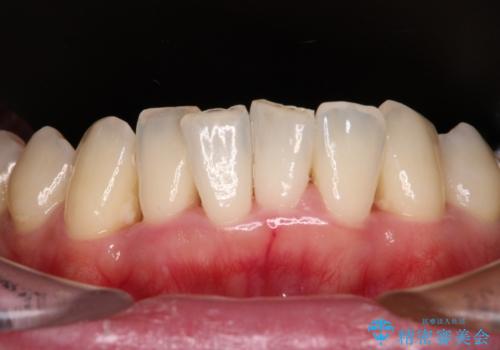

下顎前歯の叢生も気になっており、矯正治療も並行して進めていくこととしました。

多くの外科処置を行ったため、治療期間も長くなり、患者様の負担は非常に大きなものとなりましたが、明るく健康的な口元となり、患者様には大変満足していただけました。